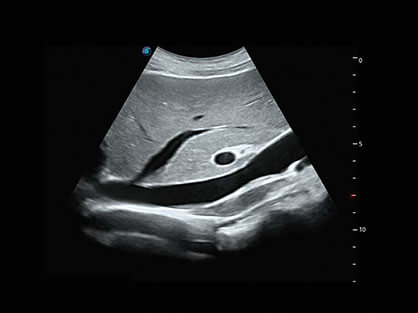

结合新葡的京集团8814检测站超宽频带探头技术优势,能够更好地获得高分辨力与高穿透力的平衡,保证图像质量,为临床诊断保驾护航。

微米成像技术提升了对组织斑点噪声信号的抑制能力,并进一步强化边界信息,从而获得清晰图像。